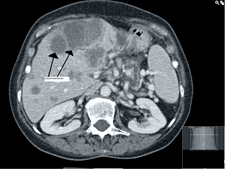

CT is a procedure of X-ray diagnostics creating cross-sectional pictures of the body. During CT an X-ray machine, consisting of an X-ray tube assembly and a radiation detector on the opposite site, continuously rotates around the body, following a circular or spiral path to obtain a multiplicity of radiographs from different directions (projections). A computer program is used to transform these projection images into cross-sectional non-overlapping pictures of high-contrast displaying tissues of different density in well distinguishable shades of grey.